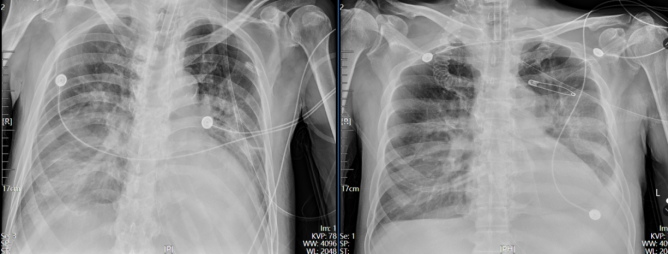

经上述治疗后,患者病情明显好转,呼吸机氧浓度及PEEP逐步下调,复查血气分析及氧合指数均改善,白细胞计数、降钙素原、氨基末端B型利钠肽前体均呈下降趋势(图4-图6)2025年12月17日予拔除气管插管,更换鼻导管吸氧,复查胸片提示肺炎较前好转(图7

7  患者2025年12月9日与12月14日胸片对比